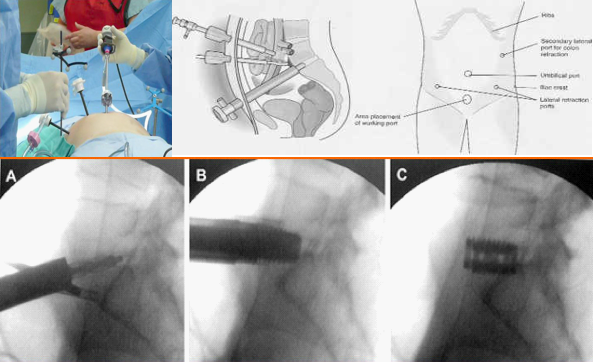

上个世纪九十年代,随着胸腔镜和腹腔镜技术的蓬勃发展,其独特的微创优势吸引了脊柱外科医师的关注,并尝试将其用于腰椎前路手术中。1995年,Zucherman首次使用腹腔镜下ALIF,结果显示[10]其具备腹腔镜手术的微创优势,但学习曲线长,技术要求高,L4/5节段尤其困难;血管损伤并发症较开放手术高[11];融合器大小受操作通道的限制;仍需后路手术增强稳定性。

正是由于以上问题,使得人们在开展该技术上存有疑虑并限制了发展,并被打上了“昙花一现”的标签。因此,在1997年,Mayer提出了小切口经肌间、腰大肌-血管自然间隙入路进行腰椎前路手术的新理念[12]。该技术在L2-S1均可采用,L4/5以上腹外侧入路,L5/S1采用下腹入路,手术创伤较传统入路明显减少,但仍然避免不了腹部大血管损伤的问题。

笔者及团队自1998年起开展了腹腔镜下腰椎融合技术,该技术可以说是现代OLIF技术的全内镜下的“版本”。然而,在临床应用过程中,腹腔镜锁孔下操作存在着上述诸多问题,为兼顾微创的同时改善手术的便利性与实用性,2002年起,腰椎前路融合手术均革新为腹腔镜辅助小切口或单纯小切口方式进行。在融合器稳定性方面,由于早期缺乏自稳装置,前路术后往往需要进行后路补充固定。近年来,随着理念的进步和经验积累,涌现了附有自身稳定的融合器如LDR等。为此,结合自锁cage的应用,于2015年设计了腹前外侧入路腰椎间融合(ALLIF)技术,该入路设计简单、直接、安全。术中患者采用斜卧位,切口根据椎间隙的体表投影,贴腹直肌左外缘作4-6cm横/斜切口所经层次:腹外斜肌-腹内斜肌-腹横肌至腹膜外间隙,用常规腹部拉钩将血管及腹膜稍牵向内侧,另一拉钩置于椎体侧前、交感神经链前方,将其稍向后牵开。辅以头灯放大镜或显微镜,直接对神经结构进行减压,选用自锁型融合器,不需附加前路钉板或后路钉棒,同时对于退行性滑脱的病例,采用前侧入路方式可以获得有效的椎体复位,从而达到减压、复位、融合与稳定等“四位一体”,“一箭多雕”之目的[16,17]。